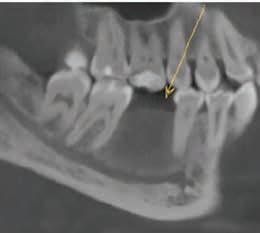

Cone-Beam Computed Tomography

Cone-beam computed tomography (CBCT) has become an essential tool in the field of dentistry, as it offers a highquality, 3-dimensional (3D) image.25 It is superior to bone sounding and conventional 2-dimensional radiography in the assessment of CEJ and bone morphology, as well as detecting abnormal root anatomy and bony dehiscence or fenestrations.13 Furthermore, it is more comfortable for patients and less invasive than bone sounding.26 Leung and colleagues reported on the greater accuracy of CBCT in identifying the CEJ than identifying alveolar bone margin.26 This was due to the fact that the CEJ is the junction between enamel and cementum, which have different densities, and the latter is the interface between cementum and bone, which have similar densities. In addition, greater accuracy was reported in detecting bone fenestration than dehiscence.

Grimard and colleagues reported a strong correlation between CBCT and direct surgical measurements of the hard tissues.27 Although CBCT was found to underestimate the distance from CEJ to the base of bone defect, it precisely estimated the distance between CEJ and alveolar crest. In contrast, intraoral PA radiographs were found to be less reliable than CBCT, as they underestimated the measurements of all investigated parameters considerably.27 Batista and colleagues suggested the use of CBCT for the diagnosis and presurgical planning of APE cases, as it provides accurate measurements related to the CEJ and alveolar bone crest, in addition to the actual anatomic crown length.4

The use of a digital workflow to treat patients with APE has been proposed in situations with restorative treatments, as well as when no restorative treatment is anticipated.38,39 In this method, a CBCT scan is acquired to analyze the level of the alveolar bone crest in relation to the CEJ. An intraoral scan is acquired to aid in fabricating a surgical guide. Digital Imaging and Communications in Medicine files obtained from the CBCT are converted to Standard Tessellation Language format and then superimposed with Standard Tessellation Language files acquired from the intraoral scan. The level of the CEJ is then marked (Figure 5) to guide the gingivectomy incision line, followed by a second line 3 mm apical to the CEJ line to guide the bone resection.

Figure 5. After superimposition of the cone-beam computed tomographic scan and intraoral scan, the cementoenamel junction and future bone level are marked. Reproduced from Alhumaidan A, Alqahtani A, al-Qarni F. 3D-printed surgical guide for crown lengthening based on cone beam computed tomography measurements: a clinical report with 6 months follow up. Appl. Sci. 2020;10(16):5697, CC-BY 4.0. https://doi. org/10.3390/app10165697.39